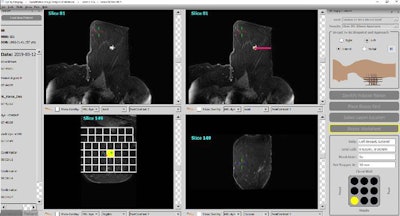

The MRI guidance breast biopsy software plugin is the latest addition to Qlarity's QuantX breast imaging computer-aided diagnosis platform. The plugin allows radiologists to plan MRI-guided breast interventions such as breast biopsy. It uses information from MR images to calculate the precise location and depth of a particular lesion and then recommends the ideal location and depth for inserting a biopsy needle.